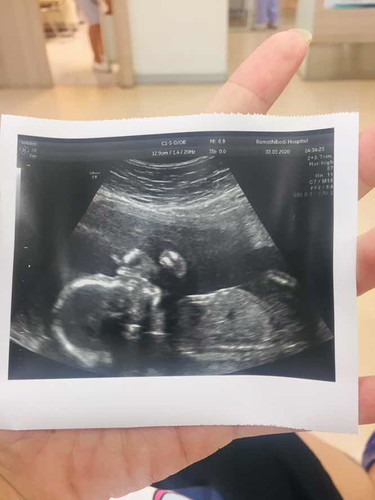

5เดือน1วัน

อาจารย์หมอบอกว่าน่าผู้ชาย แต่ไม่แน่ชัด เพราะเด็กหนีบไว้ เอาก้นบัง ขี้อายจังเลย